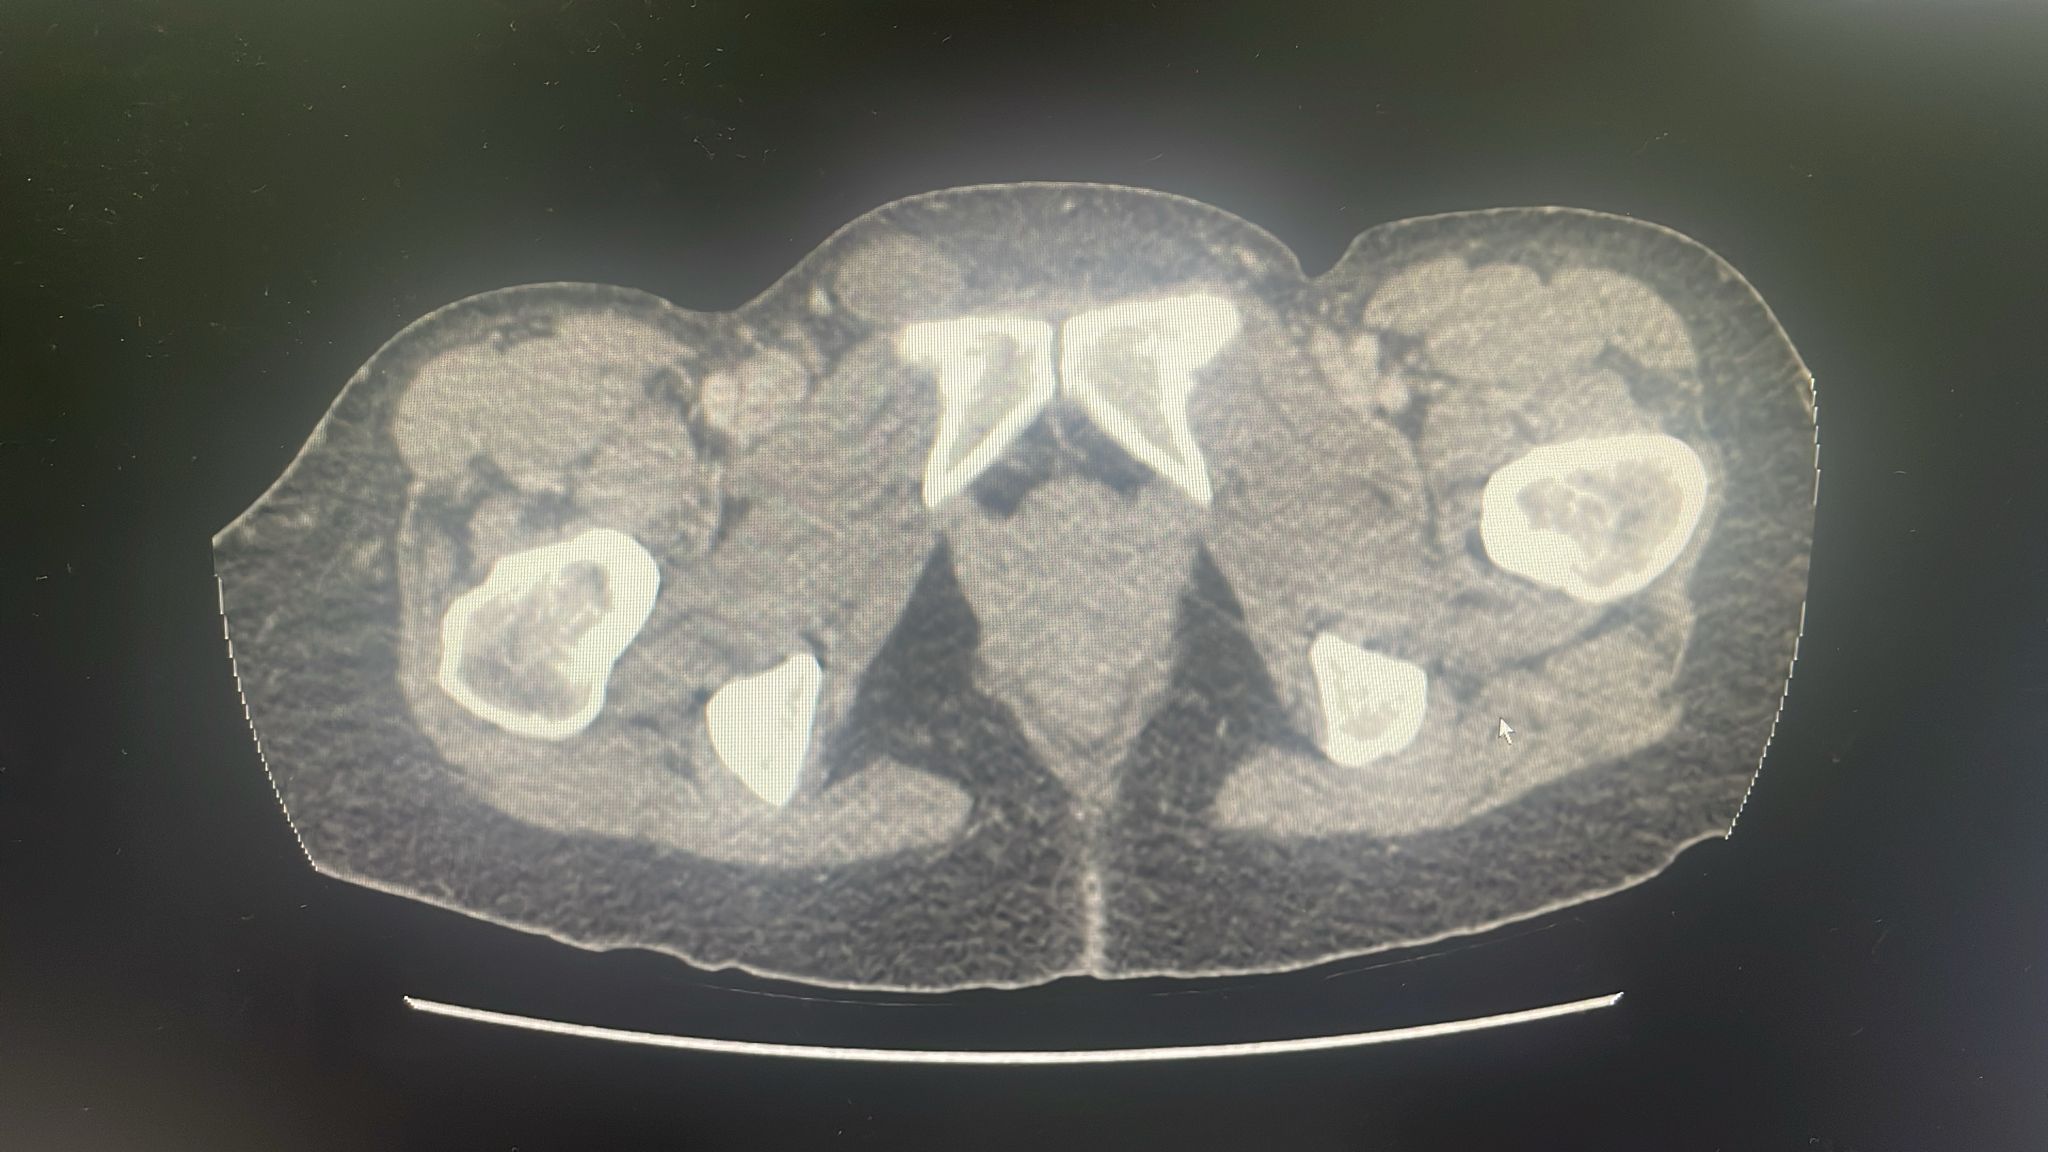

Dada la ausencia de dolor en tumoración inguinal, pero con la sospecha de obstrucción intestinal 2º a hernia inguinocrural derecha incarcerada, se decide realización de TAC abdomen, que confirma obstrucción intestinal con cambio de brusco de calibre en hernia crural derecha que contiene asa de íleon distal con hiporrealce parietal en su parte declive que podría traducir sufrimiento a este nivel.